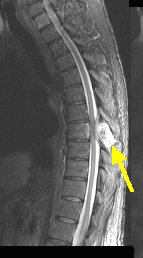

Pre-contrast sagittal T1 wtd.MRI of the thoracic spine

Low signal (dark)

Mass on T1

Sagittal T2 wtd. MRI

Mass is bright on T2 and shows compression of cord (black)

Surrounded by CSF (bright)

Post contrast sagittal T 1 wtd. MRI

Post contrast shows enhancement of mass

Bony metastasis from renal cell carcinoma with epidural tumor producing cord compression

Findings: Bony metastasis involving the T 8 vertebral body, right pedicle/transverse process and spinous process (arrow in A,B,C,D) with epidural tumor producing marked degree of cord compression (red arrow).